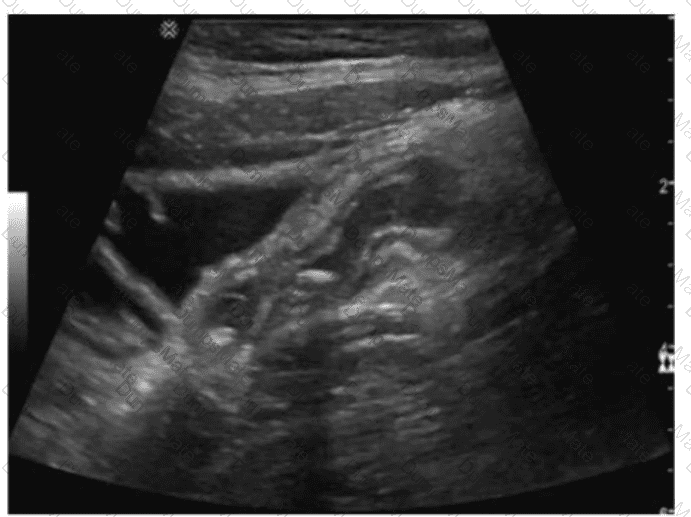

Questions 24

Which renal anomaly is demonstrated on this image?

AB-Abdomen Question 24

Options:

A.

Duplicated collecting system

B.

Crossed renal ectopia

C.

Horseshoe kidney

D.

Pelvic kidney

Buy Now